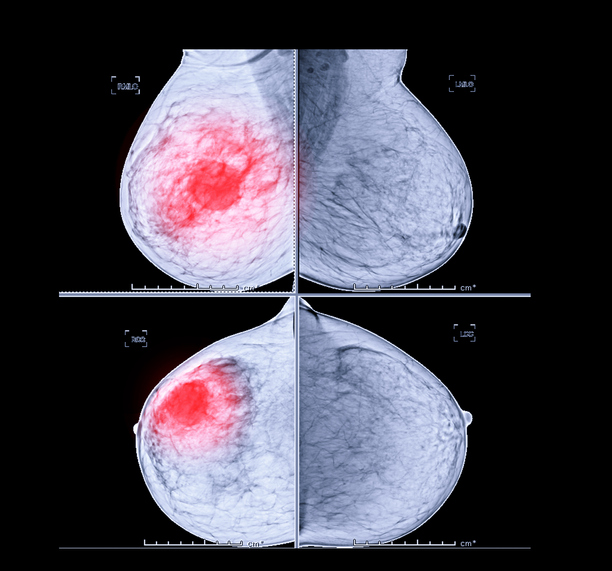

✔유방암 초기 증상 - 유방 결절 및 덩어리

유방에 있는 2cm 길이의 덩어리를 결절이라고 하고 이 크기보다 큰 것을 덩어리라고 합니다. 덩어리는 가장 흔한 증상으로 유방암 증상의 약 70%를 차지합니다. 흔히 유방 덩어리를 만질 때 통증이 없다고 생각하는데 이는 잘못된 것입니다. 대부분의 덩어리는 통증이 없으므로 젊은 여성이 자가 검진을 통해 덩어리를 느끼면 암이라고 생각하고 병원에 가는 것이 좋습니다. 20대의 경우 유방암 발병률은 2.2%입니다.